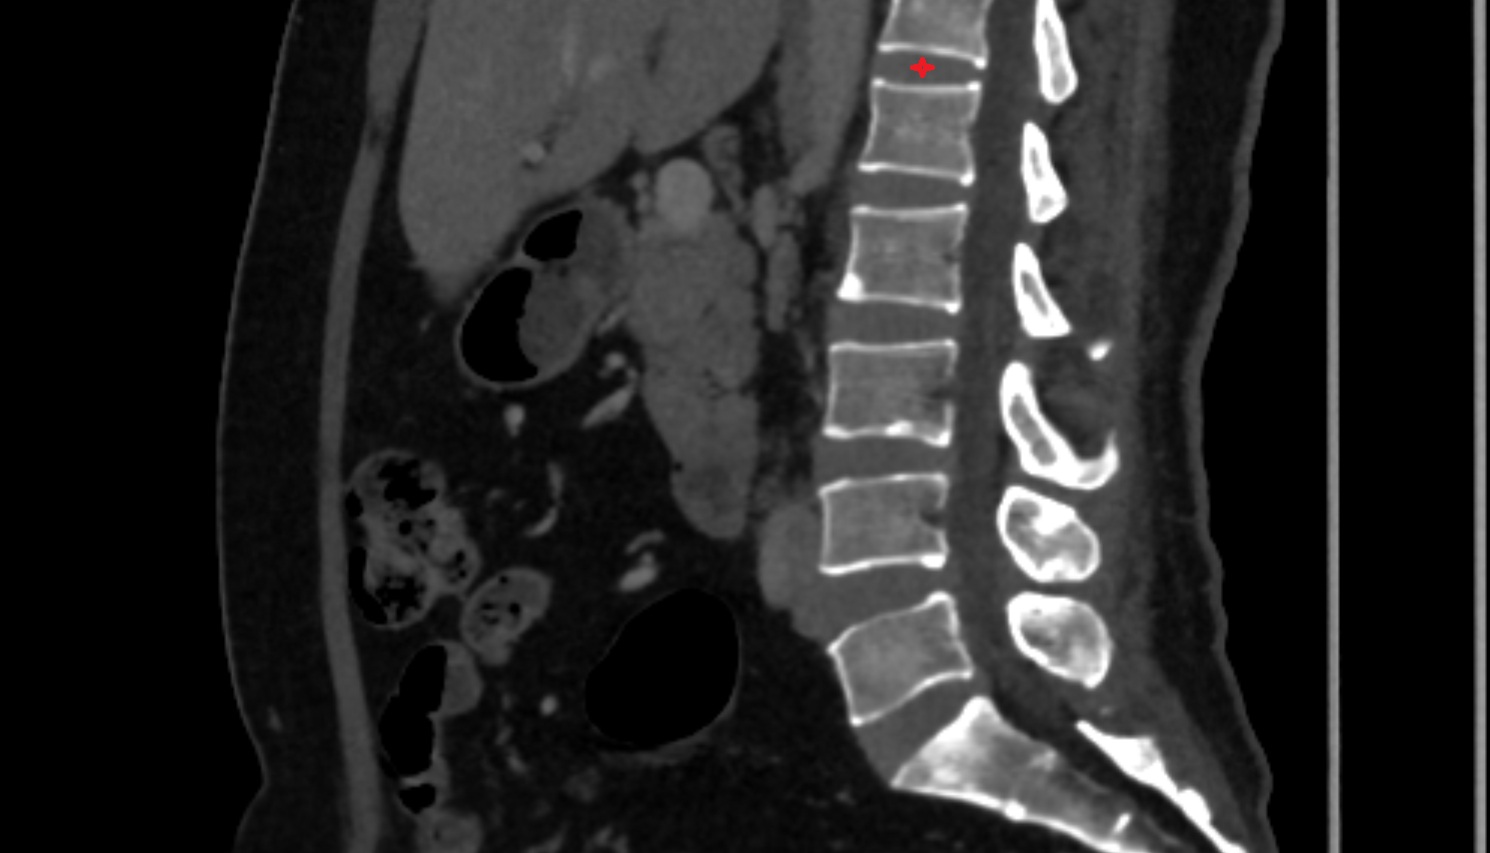

CT image

T12 –L1  Intervertebral Disc  CT sagittal  anatomy  image-img-00000-00000